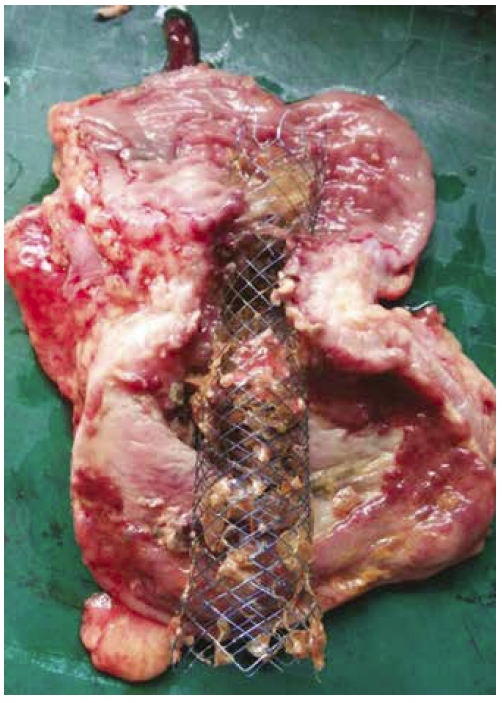

La utilización de SCA ha demostrado reducción de la morbilidad, mortalidad y estadía hospitalaria en comparación con la cirugía.13 Si bien el éxito del procedimiento es variable según los diversos centros, Watt y col. evaluaron mediante una revisión sistemática la colocación de SCA en 1785 pacientes con obstrucción intrínseca, y reportaron un éxito técnico y clínico del 96,2% y 92% respectivamente.14 En nuestra serie en dicha población, el éxito técnico y clínico fue 100% y 93% respectivamente. El procedimiento resultó seguro, sin complicaciones durante la colocación y con una tasa de migración del 8,8%, homologable a lo descripto en 2 revisiones sistemáticas donde la tasa de migración fue entre 10 y 12%.15, 16 Entre las potenciales complicaciones posteriores al procedimiento se describen el dolor, el sangrado, la reestenosis y la perforación, siendo esta última la más grave. La tasa de perforación en la literatura es de un 4%, equiparable al 2,9% de la presente serie.15 Los factores conocidos asociados a la perforación son la dilatación con balón y la quimioterapia con drogas antiangiogénicas,17 siendo esta última un factor posiblemente asociado a la única perforación encontrada en esta serie (Figura 2). No obstante, ninguno de los pacientes con dilataciones con balón sufrió esta complicación.

Pieza de colectomía con stent colocado

previamente.

Figura 2.

Pieza de colectomía con stent colocado previamente.